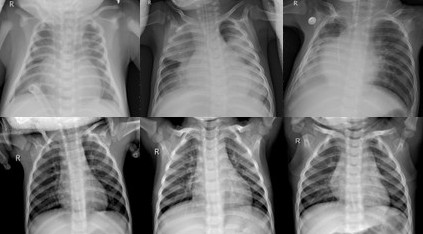

The Chest X-ray dataset comprises about 5863 frontal chest X-ray images of pediatric patients with two categories: Pneumonia (positive cases with radiological evidence of pneumonia) and Normal (healthy lungs). These images were initially taken as part of clinical routine processes at Guangzhou Women and Children’s Medical Center and have been screened for quality. This dataset gives a binary classification problem for detecting pneumonia, which typically presents as opacities in the lung fields on the X-ray image, as depicted in the Figure 2. Pneumonia may be due to bacterial or viral infections.

Refer to caption

Figure 2: Sample images from the Chest X-ray dataset showing Pneumonia and normal cases.

Figure 7: Grad-CAM visualizations for Chest X-ray: (Left) original X-ray image, (Middle) ResNet50 heatmap, (Right) DenseNet121 heatmap. DenseNet121 localizes attention to lung regions with opacities, while ResNet50 occasionally highlights unrelated areas such as the heart or ribs.

In chest X-ray pneumonia detection (Figure 7), similar differences were noticed. DenseNet121 heatmaps concentrated on lung fields with opacities, especially in the lower and middle lobes, where pneumonia is usually present in most cases. ResNet50, on the other hand, often displayed activation around the central region or silhouette of the heart, with some models even producing attention around the diaphragm or rib structures. While both models returned accurate predictions, DenseNet’s concentration was more common in radiological signs of pneumonia, suggesting that its feature extraction layers prioritize more relevant and meaningful pathology. This behavior suggests that DenseNet121 might also generalize better to unseen pneumonia patterns by concentrating on specific lung textures and avoiding being biased to general images or anatomical landmarks.